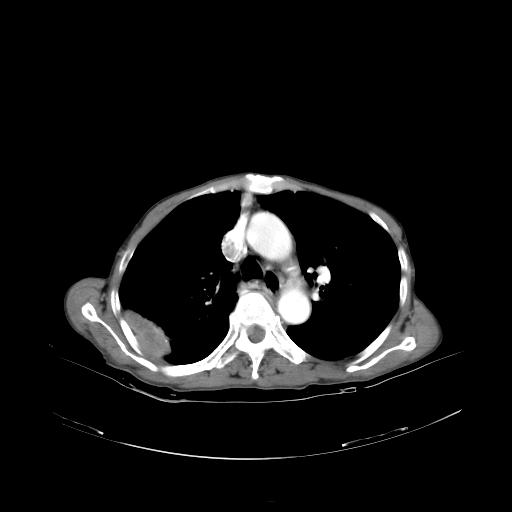

女,72岁,咳嗽一周余,突发右下肢无力二天。

pe:bp-140、80mmhg,精神可,伸舌居中,右上肢肌力正常,右下肢肌力0级,巴氏征+

来院做头颅+胸部ct平扫

遂加作增强:

胸部病变平扫35hu,增强强化至70hu

这个病人首先是胸部病变的定位到底是肺内还是肺外。仔细观察块影位于胸膜下,与胸膜间有透亮带,且近端血管未见明显推移而是引流样改变,形态分叶,说明这个病灶位于肺内胸膜下。很可能是腺癌,腺癌最易致颅内高密度转移灶。局部胸膜有侵犯。

本例颅内见多发大小不等高密度灶,有强化及水肿;另外,胸锁关节层面可能是第四胸椎及右侧肋骨起始部骨质欠连续,椎旁软组织肿胀,建议调骨窗观察。

诊断:右下肺癌伴颅内、胸椎、肋骨转移可能性最大。